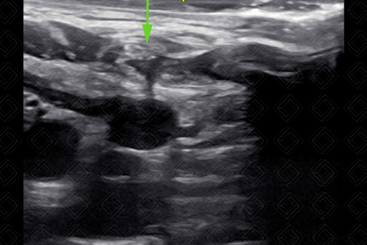

15. Punção guiada por técnica transversal (fora de plano) utilizando-se agulha 18 G (Figuras 5 a 8). [cms-watermark]

Texto alternativo para a imagem Figura 8. Visualização da agulha no interior da veia jugular interna direita (seta verde). Créditos: Dr. Igor Biscotto - Rio de Janeiro/RJ.